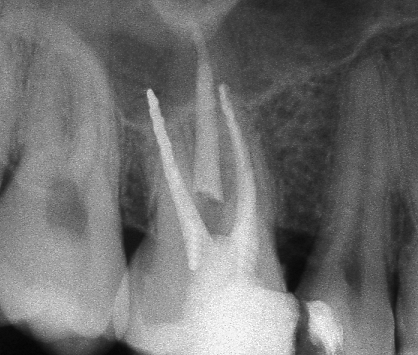

Ендодонтията е раздел от съвременната дентална медицина, който раздел изучава физиологията и патологията на вътрешната част на зъба - пулпна кухина и коренови канали. Названието на раздела идва от старогръцки - ендос - представка за вътрешност и одонтос - зъб. Това е една от научните дисциплини, които претърпяха голямо развитие през последното деситилетие.